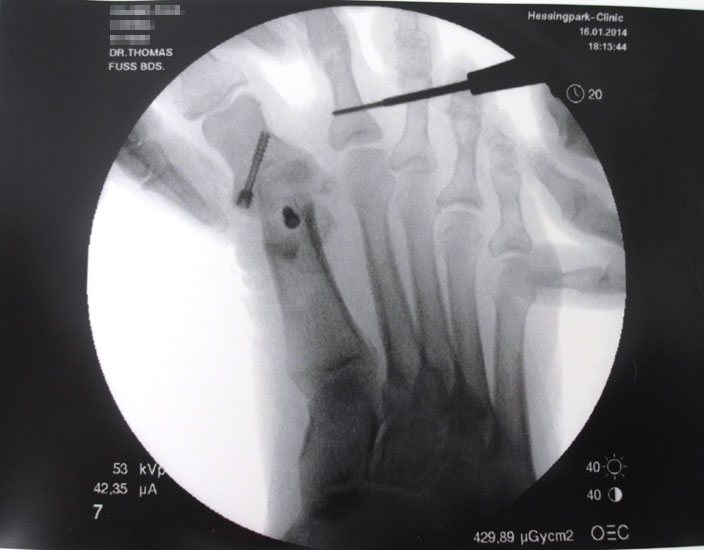

Mit dem MIS-Messer und dem Bildwandler erfolgt nun eine Positionskontrolle zur korrekten Lokalisation auf Höhe des proximalen metadiaphysären Überganges des Grundgliedes (Abb 4).

Nach Bestimmung der korrekten Osteotomiehöhe wird mit dem MIS-Messer eine je nach Seitendominanz des Operateurs dorsolaterale oder dorsomediale 3-4mm lange Inzision über dem proximalen Grundglied durchgeführt.

Im Anschluss erfolgt das Einbringen der Fräse nach plantar unter das Grundglied, auf steten Knochenkontakt sollte geachtet werden. Unter Bildwandler sollte zusätzlich zur korrekten metadiaphysären Lokalisation der Osteotomie  auch auf eine Positionierung der Fräse im rechten Winkel zum Schaft geachtet werden, zusätzlich darauf, dass zum Schutz des Gefäßnervenbündels der Gegenseite die Fräse nicht zu weit über die geplante Osteotomie  auf der  Gegenseite über das Grundglied herausragt.